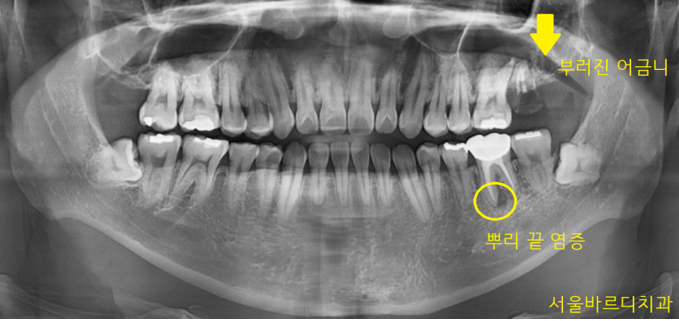

23년 11월 4일 환자분을 처음 보았습니다.

어디가 불편하신지 파악하기 위해

x-ray 사진을 한 장 찍었습니다.

2개 부위가 문제가 보이네요

두개 다 왼쪽 부위가 문제가 있었는데요.

제일 먼저 첫번째 부위

왼쪽 위 치아입니다.

맨 끝 어금니인데

육안으로 보아도 머리 부분이

거의 남아있지 않았습니다.

부러져버렸네요~

두 번째 부위

왼쪽 아래입니다.

신경치료도 되어있고

뿌리 끝에 염증도 있네요..